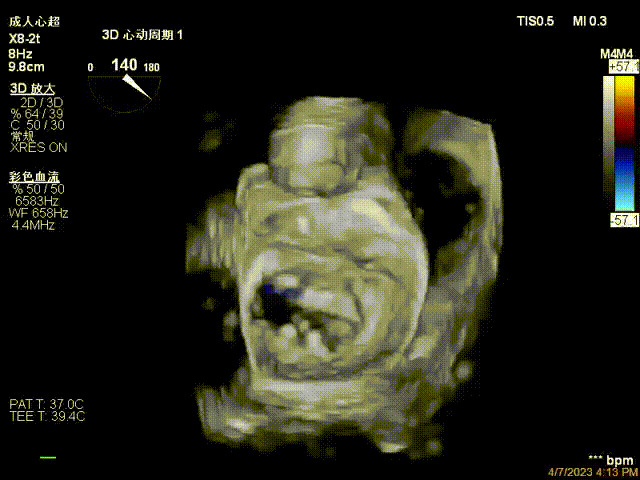

接受治療的是一例器質(zhì)性重度二尖瓣反流(DMR)患者,主訴“反復(fù)活動(dòng)后胸悶,氣促3年余”。術(shù)前超聲顯示,雙房增大,二尖瓣脫垂伴重度反流,輕度三尖瓣反流,輕度肺高壓,升主動(dòng)脈增寬。手術(shù)經(jīng)股靜脈-房間隔入路,采用全身麻醉插管,在TEE和DSA引導(dǎo)下完成房間隔穿刺。置入JensClip瓣膜夾系統(tǒng)后,在左房調(diào)整瓣膜夾的位置和軸向,后進(jìn)入左室,在TEE引導(dǎo)下捕捉二尖瓣前后瓣葉,并關(guān)閉瓣膜夾。經(jīng)TEE反復(fù)確認(rèn)手術(shù)效果后最終鎖定并釋放瓣膜夾。術(shù)后即刻超聲顯示瓣膜夾位置穩(wěn)定,功能良好,術(shù)前二尖瓣反流4+,術(shù)后0反流,肺靜脈逆流和左房壓都顯著好轉(zhuǎn),手術(shù)圓滿(mǎn)成功(以上數(shù)據(jù)都來(lái)源于醫(yī)院的臨床記錄)。術(shù)后患者狀態(tài)良好,目前已安排出院。

術(shù)后超聲顯示二尖瓣反流消失,瓣膜夾穩(wěn)定